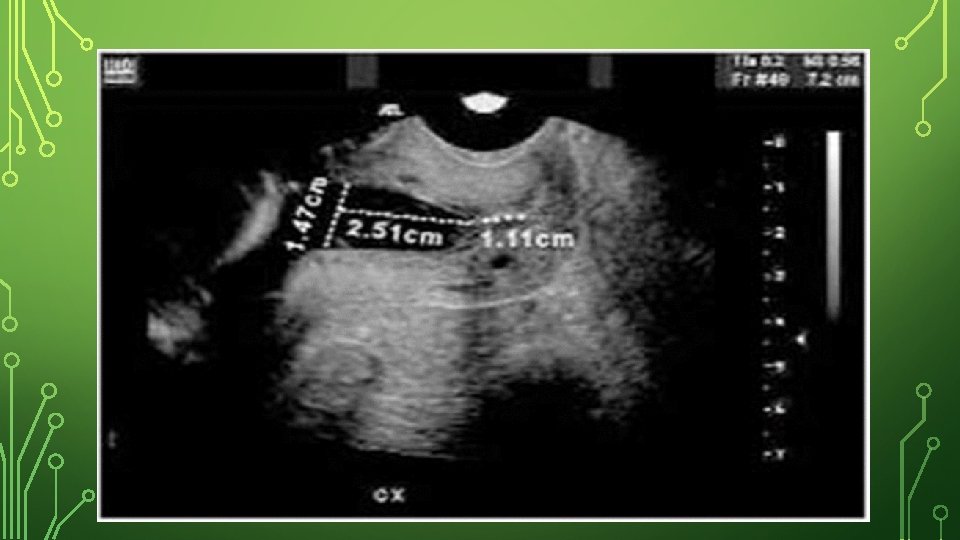

• • • Diagnosis: During pregnancy -Based on an obstetric history of recurrent second- or early thirdtrimester fetal loss with the above criteria mentioned (painless cervical dilation). • -Sudden unexpected rupture of membrane followed by expulsion of the fetus • -Pelvic exam, examine cervix to see if the amniotic sac has begun to protrude through the opening (prolapsed fetal membranes). • - In addition to history, use assessment of cervical length in second trimester to identify cervical shortening using transvaginal ultrasound. However, short cervical length has actually been shown to be a marker of preterm birth rather than cervical incompetence. • Normally, the cervix should be at least 30 mm in length. Cervical incompetence is variably defined. However, a common definition is a cervical length of less than 25 mm at or before 24 weeks of gestational age

-- A normal sagittal view of the cervix shows a “T” shaped endocervical canal vs. deviations such as Y, V, U. Y= initial effacement and subsequent V, U visualized on progressive endocervial change and cervical shortening. TVS assessments in low-risk women to screen for cervical incompetance should not be done routinely. Management should be determined by prior history.